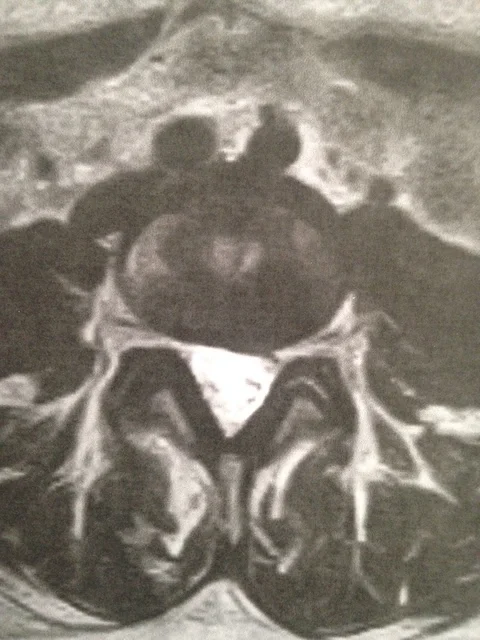

AFTER

MRI scans showing before and after spinal decompression treatment